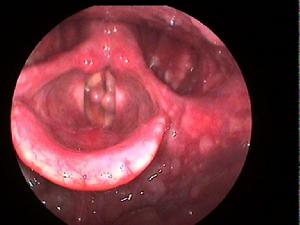

鼓膜破裂後,可突感耳痛、聽力減退、耳鳴,少量出血和耳內悶塞感。爆震傷除引起鼓膜破裂外,還可由於鐙骨強烈運動而致內耳受損,出現眩暈、噁心或混合性聾。檢查可見鼓膜多呈裂隙狀穿孔,穿孔邊緣有少量血跡,外耳道有時可見血跡或血痂。若有水樣液流出,示有顱底骨折所致腦脊液耳漏。耳聾屬傳導性或混合性。

(4) 外傷性鼓膜破裂的形態依其致傷方式的不同各有其特點;掌擊或爆震所致鼓膜穿孔形狀不一,可為梭形、裂隙形或不規則形,可見其邊緣不整齊或內翻。本組梭形及不規則形穿孔較多,邊緣內翻;器械傷所致穿孔形狀各異,本組毛線針刺傷者為圓形,另兩例尖銳物刺傷者分別為梭形及不規則形。

值得注意的是,隨著時間的推移,外傷性鼓膜破裂的情況可發生一定程度的變化,尤其繼發感染者,可失去外傷性鼓膜穿孔的特有形態,而小的破裂可在短時間內癒合,這為我們的傷情評定增加了難度。鑒於此,我們常對外傷性鼓膜破裂者,早期錄像,以記錄傷後鼓膜破裂的初期表現,為以後鑑定提供較為客觀的依據。

鼓摸破裂時情緒緊張,可不覺任何症狀。 傷後,突覺耳內轟鳴、伴有耳痛、 耳鳴、 耳聾或突然耳聾. 有少量血從外耳道流出;如伴有內耳損傷,則有眩暈、噁心和重度耳聾。檢查時可見外耳道有血跡,鼓膜有不規則的穿孔。

鼓摸破裂時情緒緊張,可不覺任何症狀。 傷後,突覺耳內轟鳴、伴有耳痛、 耳鳴、 耳聾或突然耳聾. 有少量血從外耳道流出;如伴有內耳損傷,則有眩暈、噁心和重度耳聾。檢查時可見外耳道有血跡,鼓膜有不規則的穿孔 。